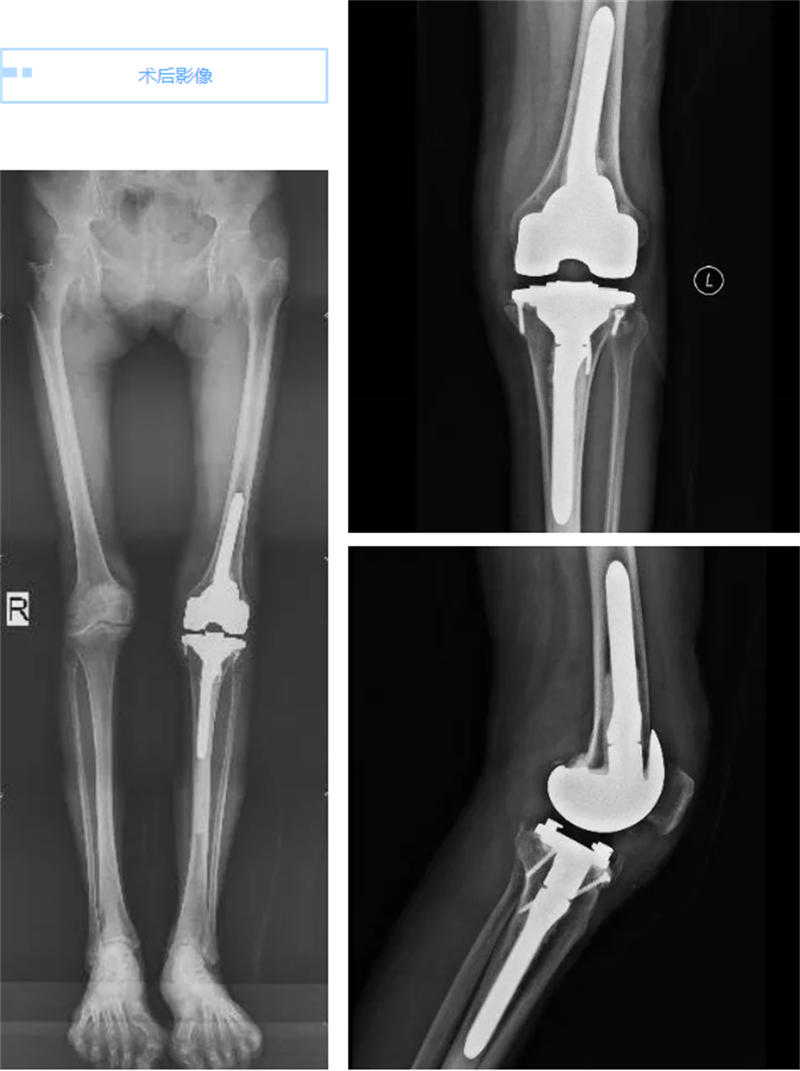

手術(shù)過(guò)程雖然復(fù)雜且技術(shù)難度極大,但在關(guān)節(jié)骨病科專家團(tuán)隊(duì)的精心操作下,手術(shù)順利完成。術(shù)后當(dāng)天,當(dāng)莫女士看到自己的左膝關(guān)節(jié)重新變直時(shí),她幾乎不敢相信自己的眼睛。次日,當(dāng)她嘗試著下地走路時(shí),發(fā)現(xiàn)膝關(guān)節(jié)竟然不再疼痛了,想到出院后能跟姐妹們一起跳廣場(chǎng)舞,莫女士笑得合不攏嘴,她仿佛重獲了新生,對(duì)未來(lái)充滿了期待。周圍的病友們也紛紛向莫女士送上了祝福,夸贊她仿佛重回了“18歲”。

在關(guān)節(jié)骨病科團(tuán)隊(duì)的精心治療和護(hù)理下,莫女士的康復(fù)進(jìn)展順利,她不僅恢復(fù)了健康,更重要的是,她找回了對(duì)生活的熱愛(ài)和信心。相信在不久的將來(lái),就能在廣場(chǎng)上看到莫女士翩翩起舞的身影,盡情享受著美好生活。